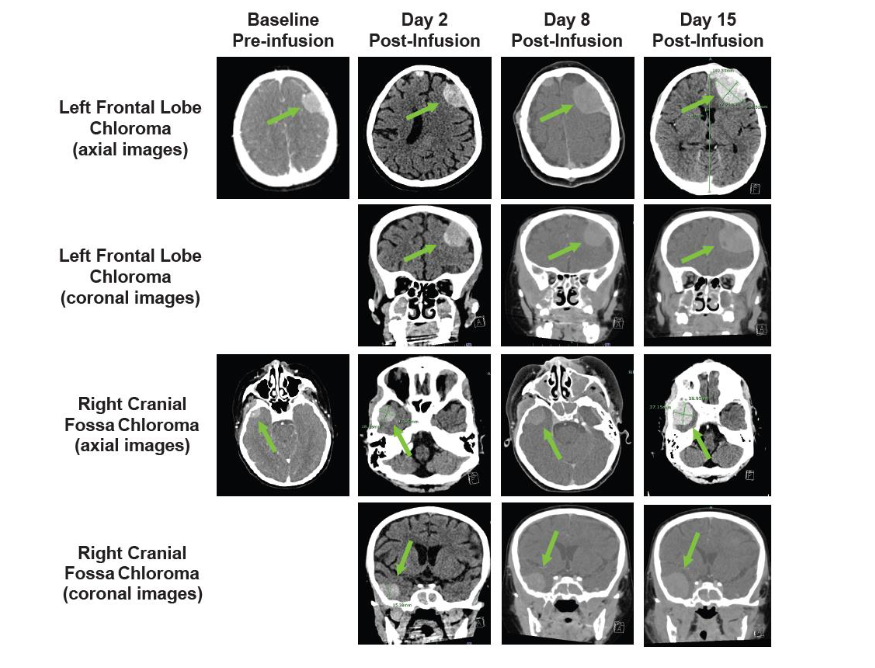

Lymphodepletion chemotherapy (fludarabine (30 mg/m²/day IV for 4 days, cyclophosphamide 500 mg/m²/day IV for 2 days) was administered in preparation for tisagenlecleucel infusion (dose: 1.9 × 10⁶ CAR+ T cells/kg [85% CAR+ T-cell viability]). On day 2, the patient developed grade 2 CRS and concern for immune effector cell–associated neurotoxicity syndrome (ICANS) with visible swelling of scalp subcutaneous chloromas, flaccid paralysis of her right lower extremity, and generalized weakness. Cranial CT (Figure 3) showed no evidence of cerebral edema but did show progressive swelling at known sites of extramedullary disease, which was presumed to be consistent with TIAP post-tisagenlecleucel infusion.

Figure 3. Cranial PET-CT and CT scans showing progressive swelling at known sites of extramedullary disease. Baseline pre-infusion (PET-CT) and post-infusion (CT) scans are shown. Arrows indicate sites of extramedullary disease; CT, computed tomography; PET, positron emission tomography.

On day 8, the patient experienced progressive swelling of the mouth and gums with gingival bleeding, oral airway obstruction, transient difficulty breathing, recurrent swelling of scalp lesions, and profound nausea/vomiting. The patient simultaneously developed lower right extremity swelling and was found to have a superficial saphenous vein thrombus on ultrasound. Cranial CT (Figure 3) showed progression of existing intracranial extramedullary sites. A marked increase in known retroperitoneal disease was also observed (not shown). Given the prior reduction in extramedullary chloromas, the patient received a third tocilizumab dose (8 mg/kg) in addition to dexamethasone (10 mg IV every 6 hours). The patient’s scalp lesions decreased in size. Lower right extremity swelling and nausea/vomiting resolved completely over 36 hours.On day 12, the patient again had lower right extremity swelling. Repeat abdominal CT (Figure 4) showed a mild increase in adenopathy, with complete inferior vena cava and right external iliac vein occlusion. The patient received siltuximab (400 mg IV every 72 h) given the substantially longer half-life than tocilizumab. Unfortunately, the patient experienced no notable response and underwent emergency radiation therapy (2 Gy over 2 consecutive days). No substantial improvement in lower right extremity swelling or size of retroperitoneal adenopathy was observed at day 15 (Figure 4).